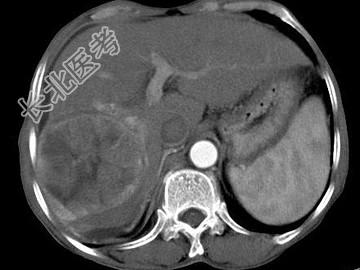

- 单项选择题女,40岁, 有口服避孕药史,肝区疼痛、腹部包块, AFP阴性,CT扫描如图, 最可能的诊断是

A、肝细胞腺瘤

B、肝再生结节

C、结节性肝癌

D、肝右叶巨块型肝癌

E、肝黄色肉芽肿